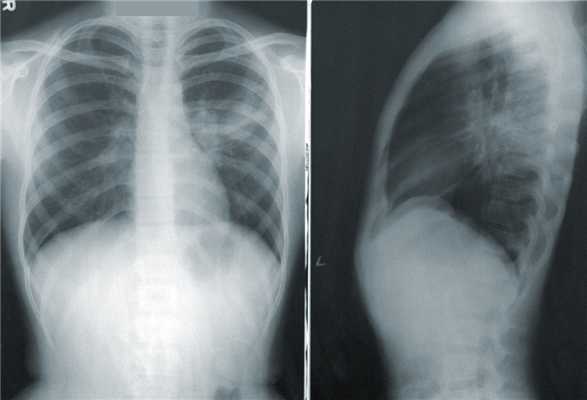

Обследование больного следует начинать с производства снимков в двух взаимно перпендикулярных проекциях, лучше на пленке размерами 35 х 43 см на аппарате «Сиреграф Д-2М» с усилителем рентгеновского изображения (УРИ) на 3 рабочих места фирмы Siemens, «DX-90», фирмы Apelem или «Proteus XR/a» фирмы General Electric. Полипроекционная рентгенография позволяет судить о локализации и протяженности воспалительного процесса в легких, состоянии легких в целом, корней легких, плевры, средостения и диафрагмы. Снимок только в прямой проекции допускается для больных, находящихся в очень тяжелом состоянии.

Обзорные снимки грудной клетки выполняют при следующих технических данных: от фокуса рентгеновской трубки до пленки — 1,5 м (телеснимок) с применением отсеивающего растра 12; напряжение на рентгеновской трубке — 70-95 кВ, анодный ток — 100-250 мА, выдержка — 0,1-0,3 с. Однако снимки грудной клетки следует производить с использованием техники жесткого излучения (анодное напряжение — 120 кВ, выдержка — 0,02 с). На таких снимках прослеживается легочный рисунок в норме до периферии, выявляются патологические образования за тенью сердца, диафрагмы и мелкие субплевральные, которых не видно на обычных снимках. При этом появляется возможность интерпретировать интерстициальную структуру. Эффективная дозовая нагрузка составляет не более 1,0 мЗв.